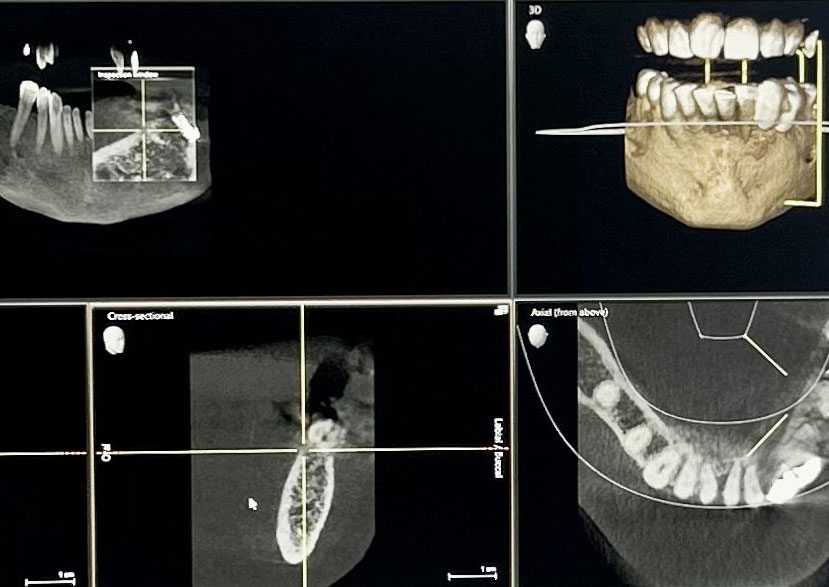

The process involves placing a small titanium post in your jawbone, where it naturally bonds with the bone over time to create a secure foundation, just like a real tooth root.

Once the implant is fully integrated, a custom-made crown or bridge is attached, designed to match your natural teeth in both look and feel.